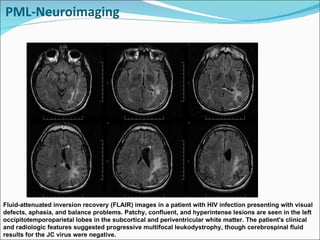

PML-Neuroimaging Fluid-attenuated inversion recovery (FLAIR) images in a patient with HIV infection presenting with visual defects, aphasia, and balance problems. Patchy, confluent, and hyperintense lesions are seen in the left occipitotemporoparietal lobes in the subcortical and periventricular white matter. The patient's clinical and radiologic features suggested progressive multifocal leukodystrophy, though cerebrospinal fluid results for the JC virus were negative.